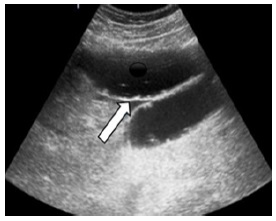

Una ecografía abdominal (Figura 2a), indica distensión de asas intestinales, compatible con una obstrucción intestinal; la tomografía de abdomen simple (Figura 2b), muestra un lito de más o menos 5 cm en intestino delgado, compatible con probable íleo biliar.

Para el diagnóstico se solicitan estudios de imagen, como una radiografía de abdomen y en los hallazgos se busca la famosa tríada de Rigler, que consiste en la presencia de cálculos radiopacos (presentándose en menos del 10 % de los casos), neumobilia (signo de Gotta-Mentschler), y distensión de las asas intestinales; la presencia de 2 de los 3 signos establece el diagnóstico11; en nuestro caso se puede evidenciar claramente 2 criterios que son, presencia de lito y datos de distención intestinal. El estudio de preferencia es la tomografía de abdomen, la cual puede confirmar el diagnóstico, permitir localizar el sitio de obstrucción, determinar presencia de neumobilia, y planificar el tratamiento12; en el caso de nuestro paciente este examen claramente reflejo el diagnostico en mención.